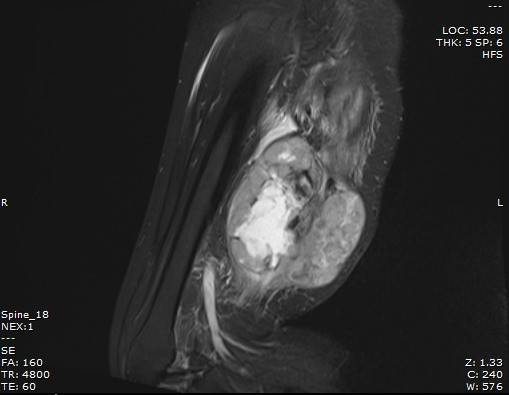

Chị quyết định đến thăm khám tại Bệnh viện Bãi Cháy với hi vọng sẽ được phẫu thuật và bảo tồn chi thể. Kết quả chụp cộng hưởng từ (MRI) tại Bệnh viện Bãi Cháy xác định trong cơ vùng đùi phải có khối kích thước lớn 12,5x9,7cm, xâm lấn thần kinh hông to đoạn 1/3 dưới đùi phải. Các bác sĩ đã hội chẩn chuyên khoa ung bướu và chấn thương chỉnh hình, quyết định phẫu thuật lấy bỏ khối sarcoma.

| Kết quả chụp cộng hưởng từ (MRI) tại Bệnh viện Bãi Cháy xác định trong cơ vùng đùi phải có khối kích thước lớn 12,5x9,7cm |